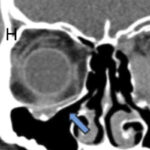

First-in-human procedure with Osteopore technology. Osteopore (OSX)’s implant carried out in a top hat configuration as a burr hole cover.

First-in-human patient specific implant with Osteoplug (plug and strip configuration) for craniotomy.

First-in-human patient specific implant with PCL-TCP for cranioplasty.